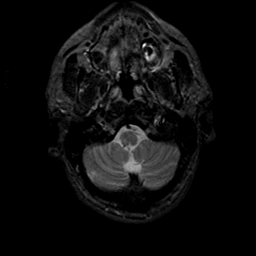

MR Study #21, November 3, 1991 -- Slice #5